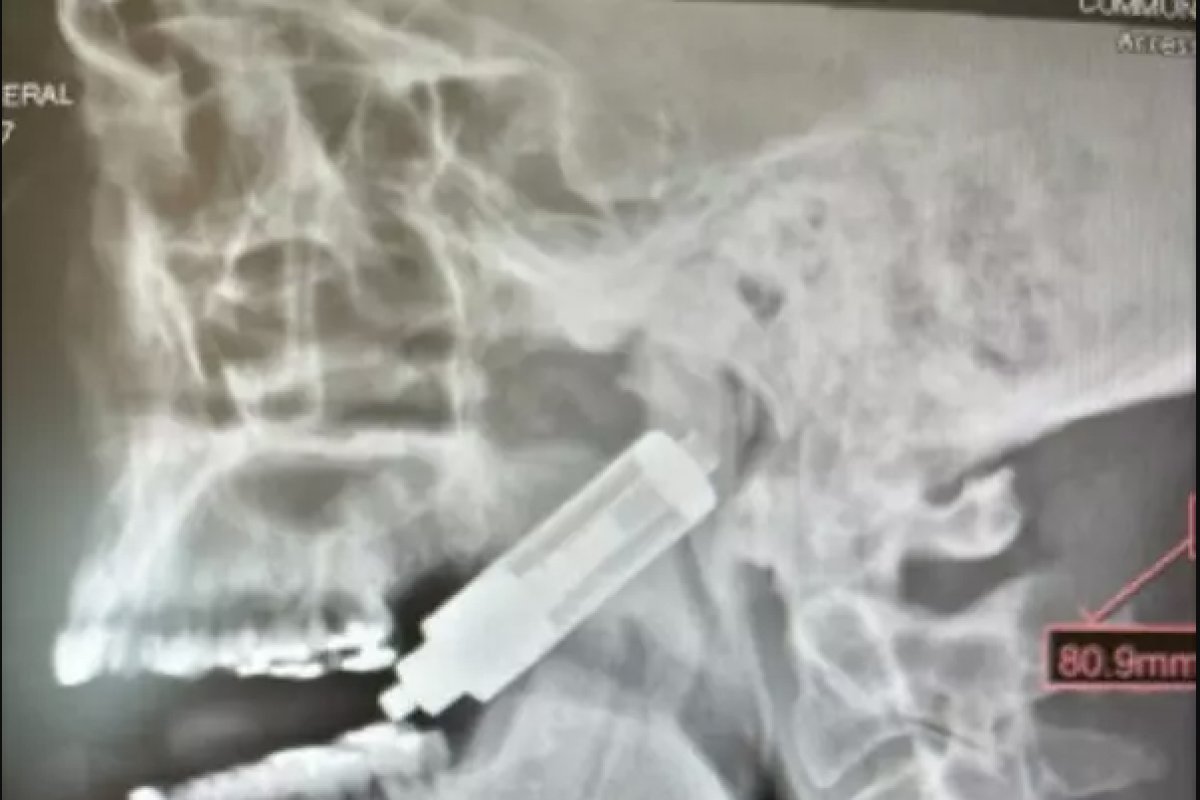

Um homem ficou ferido após o vape em que ele fumava explodir e ficar cravado no crânio. O caso foi divulgado pela revista científica “oooo journal” no dia 11 de março, mas só viralizou nesta semana. A identidade do paciente e o local onde aconteceu o incidente não foram divulgados.

De acordo com o estudo, o homem tragava a fumaça do cigarro eletrônico quando o dispositivo explodiu. Com a pane no aparelho, o vape perfurou a garganta do paciente e ficou preso ao crânio.